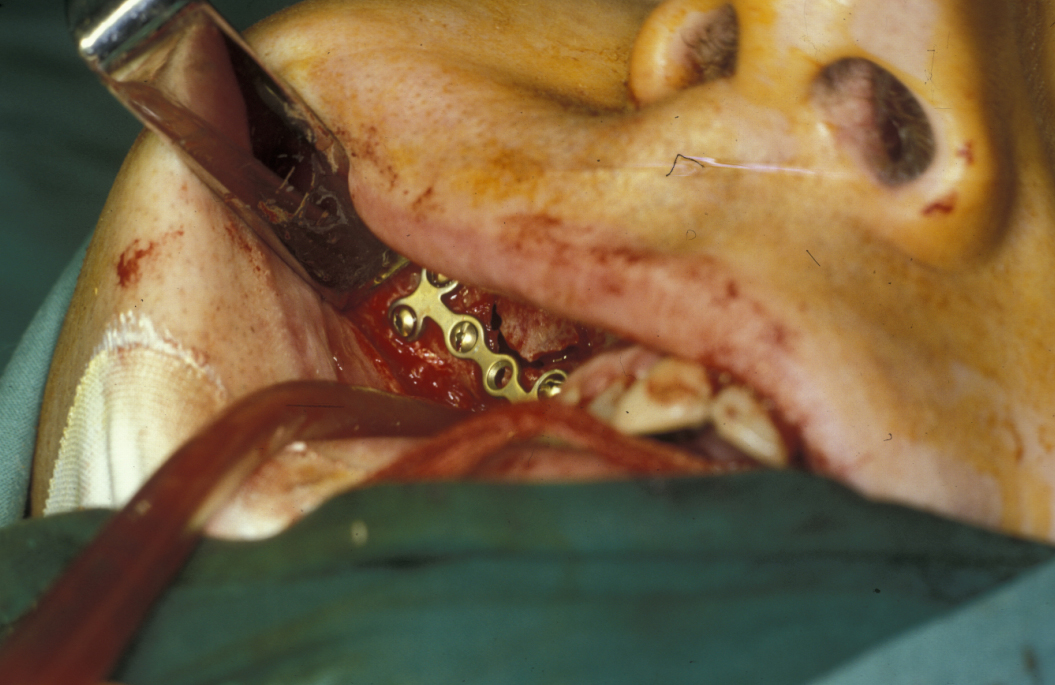

Under direct vision via buccal sulcus incisions (incision in the depression between cheek and arch of jaw) the mandibular fracture is exposed and reduction confirmed (see Figure 3).

Fixation is undertaken with titanium mandibular plates. According to Champy’s principles, in the mandibular symphyseal and parasymphyseal (the middle region of the mandible) region two mandibular plates are required, one just below the level of incisor/premolar apices and above the mental foramen and one as low down on the buccal surface as possible parallel to the lower border of the mandible. This is shown in Figure 4.